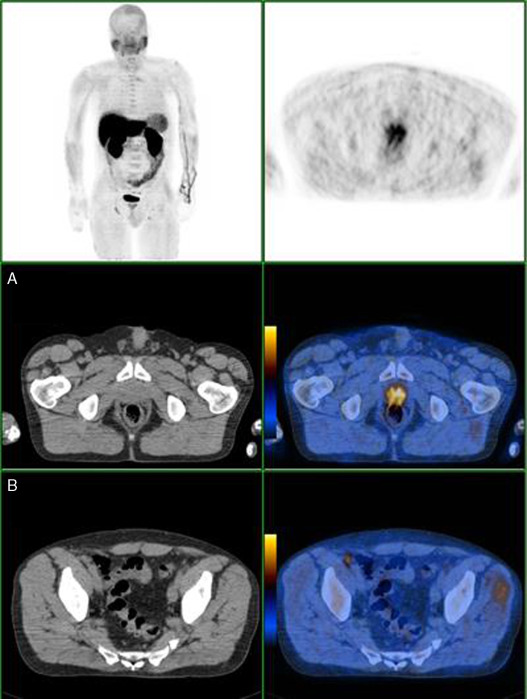

Nas Figura 1 , Figura 2 , Figura 3  ;  Figura 4 apresentam‐se 4 exames PET/CT com FCH‐F18 realizados em contexto de estadiamento inicial de CaP. Na figura 1 encontra‐se um doente apenas com doença prostática com PSA de estadiamento de 48 ng/mL. Na figura 2 apresenta‐se um doente com doença prostática e metastização ganglionar pélvica com PSA de estadiamento de 40 ng/mL. Na figura 3 , o doente apresentava doença prostática e metastização ganglionar à distância e tinha um PSA de estadiamento de 43 ng/mL. Na figura 4 o doente apresenta doença prostática e metastização óssea, e tinha uma PSA de 11 ng/mL.

Doente com CaP com PSA de 48ng/mL, com doença prostática. Sem alterações ...

Figura 1.

Doente com CaP com PSA de 48 ng/mL, com doença prostática. Sem alterações suspeitas de metastização loco‐regional ou à distância.